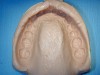

Figure 2  Cast is trimmed with the palatal area removed.

Microstone golden ADA type III, Whip Mix Corporation, is used for pouring up the cast. When pouring up the impression, care must be taken to capture all of the vestibular regions. A base is not necessary. After the cast has hardened, it will be trimmed carefully to the vestibular borders. It is important to maintain the vestibular borders to allow for the mouthguard design to extend into these areas, increasing surface adaptation, which increases retention and protection of the alveolar bone.30 The model also should be trimmed to remove the palatal area (Figure 2). This will ensure proper adaptation of the mouthguard material during the fabrication stage. A final grooming of the cast is next to remove any bubbles.